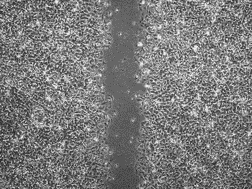

PIXCELL BIOM™ Xác minh lần 3

Đã hoàn thành các thử nghiệm lâm sàng chính thức với các kích thích bên ngoài cực độ

Sau khi tác động các kích thích bên ngoài nhân tạo vào cả hai bên má của đối tượng, chất thử nghiệm (PixelBiome™) được bôi

lên một vùng để kiểm tra mức độ làm dịu vùng da bị kích ứng.

-

Ngay sau khi điều tra

Ngay sau khi điều tra -

Sau 1 ngày sử dụng sản phẩm

Sau 1 ngày sử dụng sản phẩm -

Sau 3 ngày sử dụng sản phẩm

Sau 3 ngày sử dụng sản phẩm

Kết quả thực nghiệm

Trong nhóm đối chứng thử nghiệm sử dụng dung dịch gốc PixelBiome™, các tác động đáng kể đã được xác nhận về kết cấu da (độ nhám), độ bóng, độ trong suốt, màu sắc và

độ ẩm sau khi kích thích bên ngoài .

(Cơ quan nghiên cứu: Trung tâm nghiên cứu lâm sàng về da KSRC Hàn Quốc & Bệnh viện Bundang, Đại học Quốc gia Seoul, Khoa Phẫu thuật thẩm mỹ / 15 tháng 2 năm 2022 – 21 tháng 4 năm 2022 / 21 đối tượng)